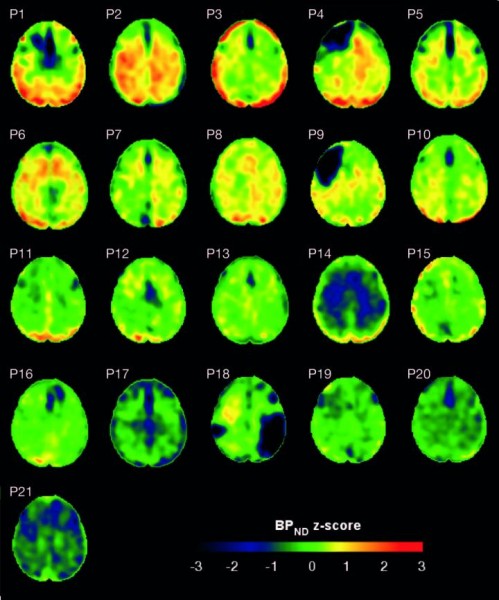

Maps showing the concentrations of tau protein (BP-ND z-score) in the brains of patients with traumatic brain injury and healthy controls. This material relates to a paper that appeared in the Sep. 5, 2019, issue of Science Translational Medicine, published by AAAS. The paper, by N. Gorgoraptis at Imperial College London in London, UK; and colleagues was titled, "In vivo detection of cerebral tau pathology in long-term survivors of traumatic brain injury." (Credit: N. Gorgoraptis et al., Science Translational Medicine (2019))

El experimento reveló que, colectivamente, la cohorte de LCT mostró más deposición de tau (como lo indica una mayor unión de flortaucipir) en comparación con 11 controles sanos y mostró un desempeño inferior en las pruebas de memoria y rendimiento cognitivo. Además, los sujetos con LCT con una mayor deposición de tau mostraron una neurodegeneración más severa y la deposición de tau también se relacionó con el daño en la materia blanca del cerebro - el tejido que aísla y nutre las neuronas. Los autores añaden que la capacidad de detectar tau en pacientes después de una LCT podría ayudar en el diseño de futuros ensayos de terapias dirigidas a tau. (Fuente: AAAS)